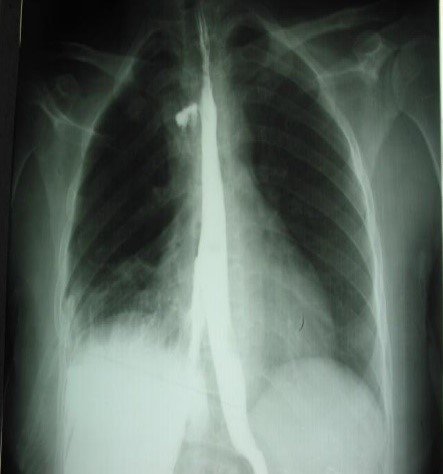

Şəkil 11. R-qramma. Kontrastın ekstravazasiyası

Endoskopiyadan sonra emfizemanın ortaya çıxması, oral kontrastlı rentgendə və ya KT-də kontrast ekstravazasiyası qida borusu perforasiyasını göstərən əlamətlərdir (Şəkil 11).